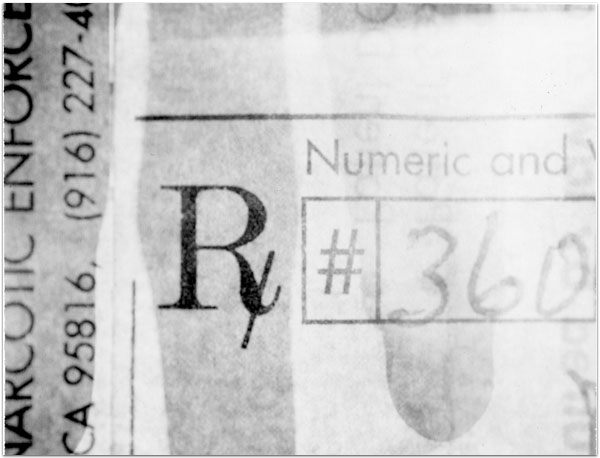

- Itis

- 2004

- 3.25″ × 4.25″

- Photographic montages of my hands & health paraphernalia on Polaroid Type 664 & 669 Film using a Daylab Printer.

- Frustrated by a lack of mobility and severe pain with my fingers, unable to accomplish any task requiring joint dexterity,

I noticed piles of health related papers strewn around. I layered these in a slide printer without removing

my hands, enlarging both onto the film.